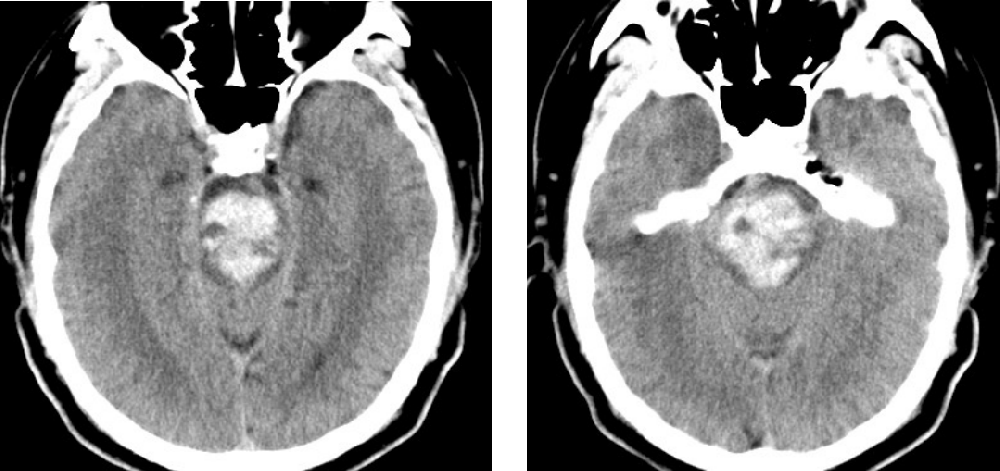

患者,男,45歲,1月2日因“突發(fā)昏迷1小時(shí)”被同事送至我院,急診CT檢查示腦干大量出血,出血量約15ml。此時(shí)患者已深度昏迷,各項(xiàng)生理反射消失,自主呼吸不穩(wěn)定,肢體強(qiáng)直并出現(xiàn)中樞性高熱,體溫40℃。因病情危重、隨時(shí)可能出現(xiàn)呼吸心跳驟停,緊急收入重癥監(jiān)護(hù)室,給予氣管插管、呼吸機(jī)通氣,維持各項(xiàng)生命指標(biāo)治療。

附手術(shù)前患者顱腦CT: